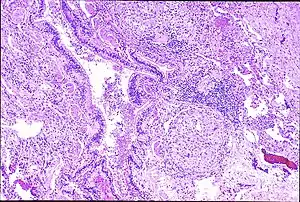

| Peribronchal non-necrotizing granuloma from berylliosis | |

Granulomas are seen in other chronic diseases, such as tuberculosis and sarcoidosis, and it can occasionally be hard to distinguish berylliosis from these disorders. However, granulomas of chronic beryllium disease will typically be non-caseating, i.e. not characterized by necrosis and therefore not exhibiting a cheese-like appearance grossly.[5]